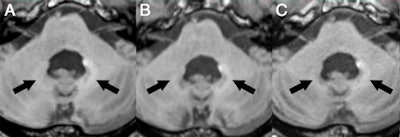

Axial MR images of a patient before (A) and after nine (B), 17 (C), 29 (D), and 41 (E) administrations of gadobutrol and gadoterate meglumine. Pre-existing hyperintensities in the dentate nucleus (most likely related to prior linear GBCA injection) are visible in all images. There is a slight decrease in hyperintensities between the baseline MRI and the MRI after 41 injections of macrocyclic GBCAs. Images courtesy of Radiology.